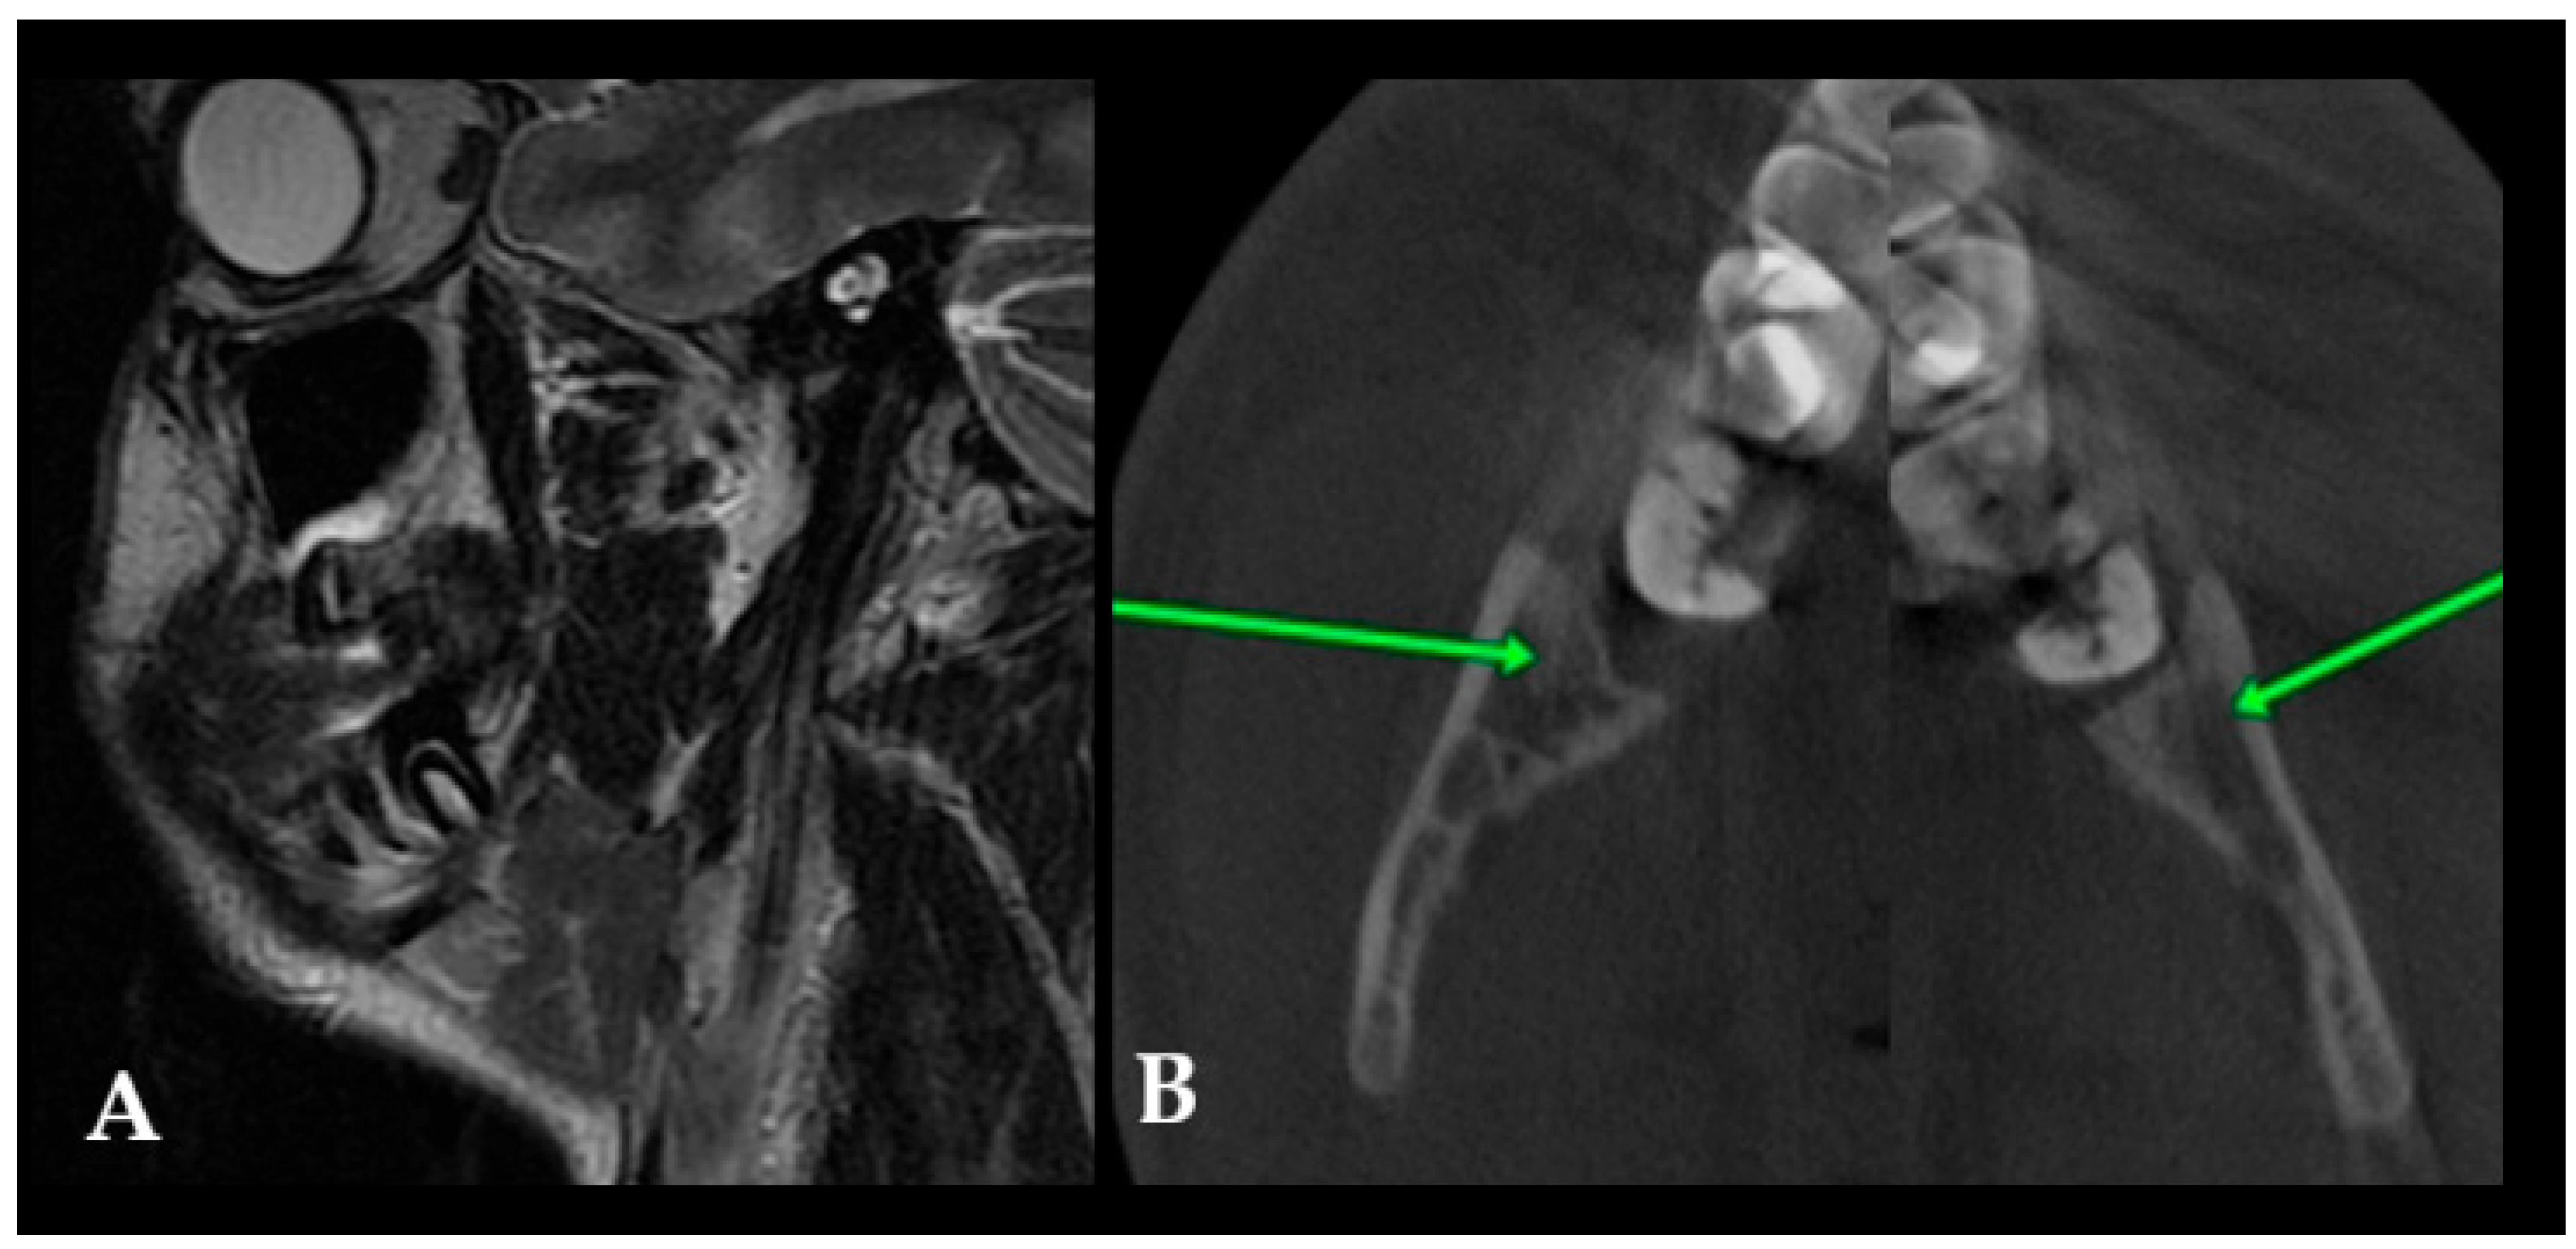

OPG is a useful initial screening tool for identifying bone cysts, lesions, and dental abnormalities. Quite often, a differentiation between dental follicles and typical cystic lesions of odontogenic and non-odontogenic origins can be assessed, as well as between solid lesions and other radiolucent, radiopaque, and mixed-appearance lesions [11,12]. Frequently, each cystic cavity in a juvenile patient should be differentiated between the following radiolucent cysts or cyst-like lesions: dentigerous cyst/follicular cyst (DC/FC), eruption cyst (EC), odontogenic keratocyst (OKC), unicystic ameloblastoma (UAM), radicular cyst, solitary bone cyst (SBC)/traumatic bone cyst, odontogenic myxoma (OM), or similar radiolucent unilocular lesions [9,10,11,12,13,14]. Routinely used OPG is quite a valuable diagnostic tool for finding any early-stage bone lesions, cysts, and tumors, and it can also be used for diagnostics with respect to teeth position, jawbone anomalies, and estimations of the dento-alveolar status of juvenile patients just before planned orthodontic treatment [15]. In cases of atypical bone architecture, such as a soap-bubble appearance, septated cystic lesions, calcifications, or irregular borders, cone-beam computed tomography (CBCT) is recommended to refine diagnoses and guide further diagnostic or surgical management. On the other hand, in juvenile patients, any enlargement or asymmetry in dental follicles surrounding retained or unerupted teeth might suggest the presence of a follicular cyst or indicate other tooth-related lesions. Sometimes, they can also cause odontogenic sinusitis when inflamed. It is worth identifying any asymmetry greater than 4 mm in any of the dental follicles and, if necessary, improving diagnostics with CBCT (Figure 1).

Figure 1. Many radiolucent lesions with well-defined borders represent cysts within the oral cavity. Each developing tooth is surrounded by a small, round radiolucent area known as the dental follicle, which is typically well defined and less than 4 mm in diameter (A). During growth, maturation, and tooth eruption, the dental follicle can remain, reduce its shape, disappear in time (blue arrows indicate the dental follicle on the left side that progressively regressed and disappeared), or form a follicular cyst (red circle). This situation occurs mostly when it is associated with totally or partially unerupted teeth (B,C). Panoramic radiography (OPG) is a useful initial screening tool and can identify various cystic and cyst-like jaw lesions of different sizes, shapes, and locations ((D)—unicystic ameloblastoma, UA). In general, retained teeth and associated cystic cavities should be further evaluated using CBCT (EG). For comparison, a representative OPG of an odontogenic myxoma is shown in (H), demonstrating typical multilocular, lobulated (the red circle highlights the soap-bubble appearance) radiolucency with internal septations, a classic pattern that helps differentiate myxoma from simple cystic lesions. On the other hand, not all found cyst-like appearances on a routine OPG are a cyst; in these cases, CBCT is recommended to ensure that the dental follicle and formation of follicular cysts or any other cyst-like lesion do not have any worrisome symptoms, such as the following: bone erosion, teeth resorption, cortical swelling, any presence of bone irregularities, septa, or a mixed radiolucent–radiopaque appearance that might suggest the formation of a possible odontogenic tumor (abbreviation from image (G): I—inferior (lower border of mandible); WL/T (mm)—location of the follicle in CBCT in millimeters).